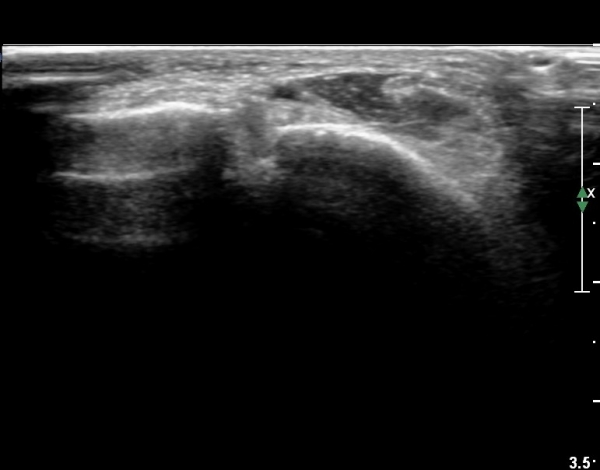

ÃÊÀ½ÆÄ °Ë»ç

Àü¹æ ¸»´Ü °æ°ñºñ°ñÀδë Á¾´Ü¸é°Ë»ç¿¡¼­ ºñ°ñ ºÎÀ§ °æ°ñºñ°ñÀδëÀÇ Àú¿¡ÄÚºÎÁ¾ÀÌ °üÂûµÇ°í

ºÎÇϰ˻翡¼­ ºñ°ñÀÇ °úµµÇÑ ¿òÁ÷ÀÓÀÌ °üÂûµÈ´Ù(»çÁø 1, 2, µ¿¿µ»ó 1).